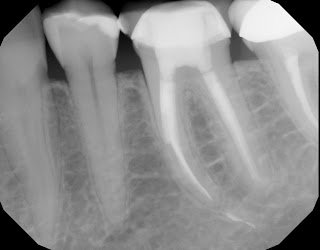

Final obturation.